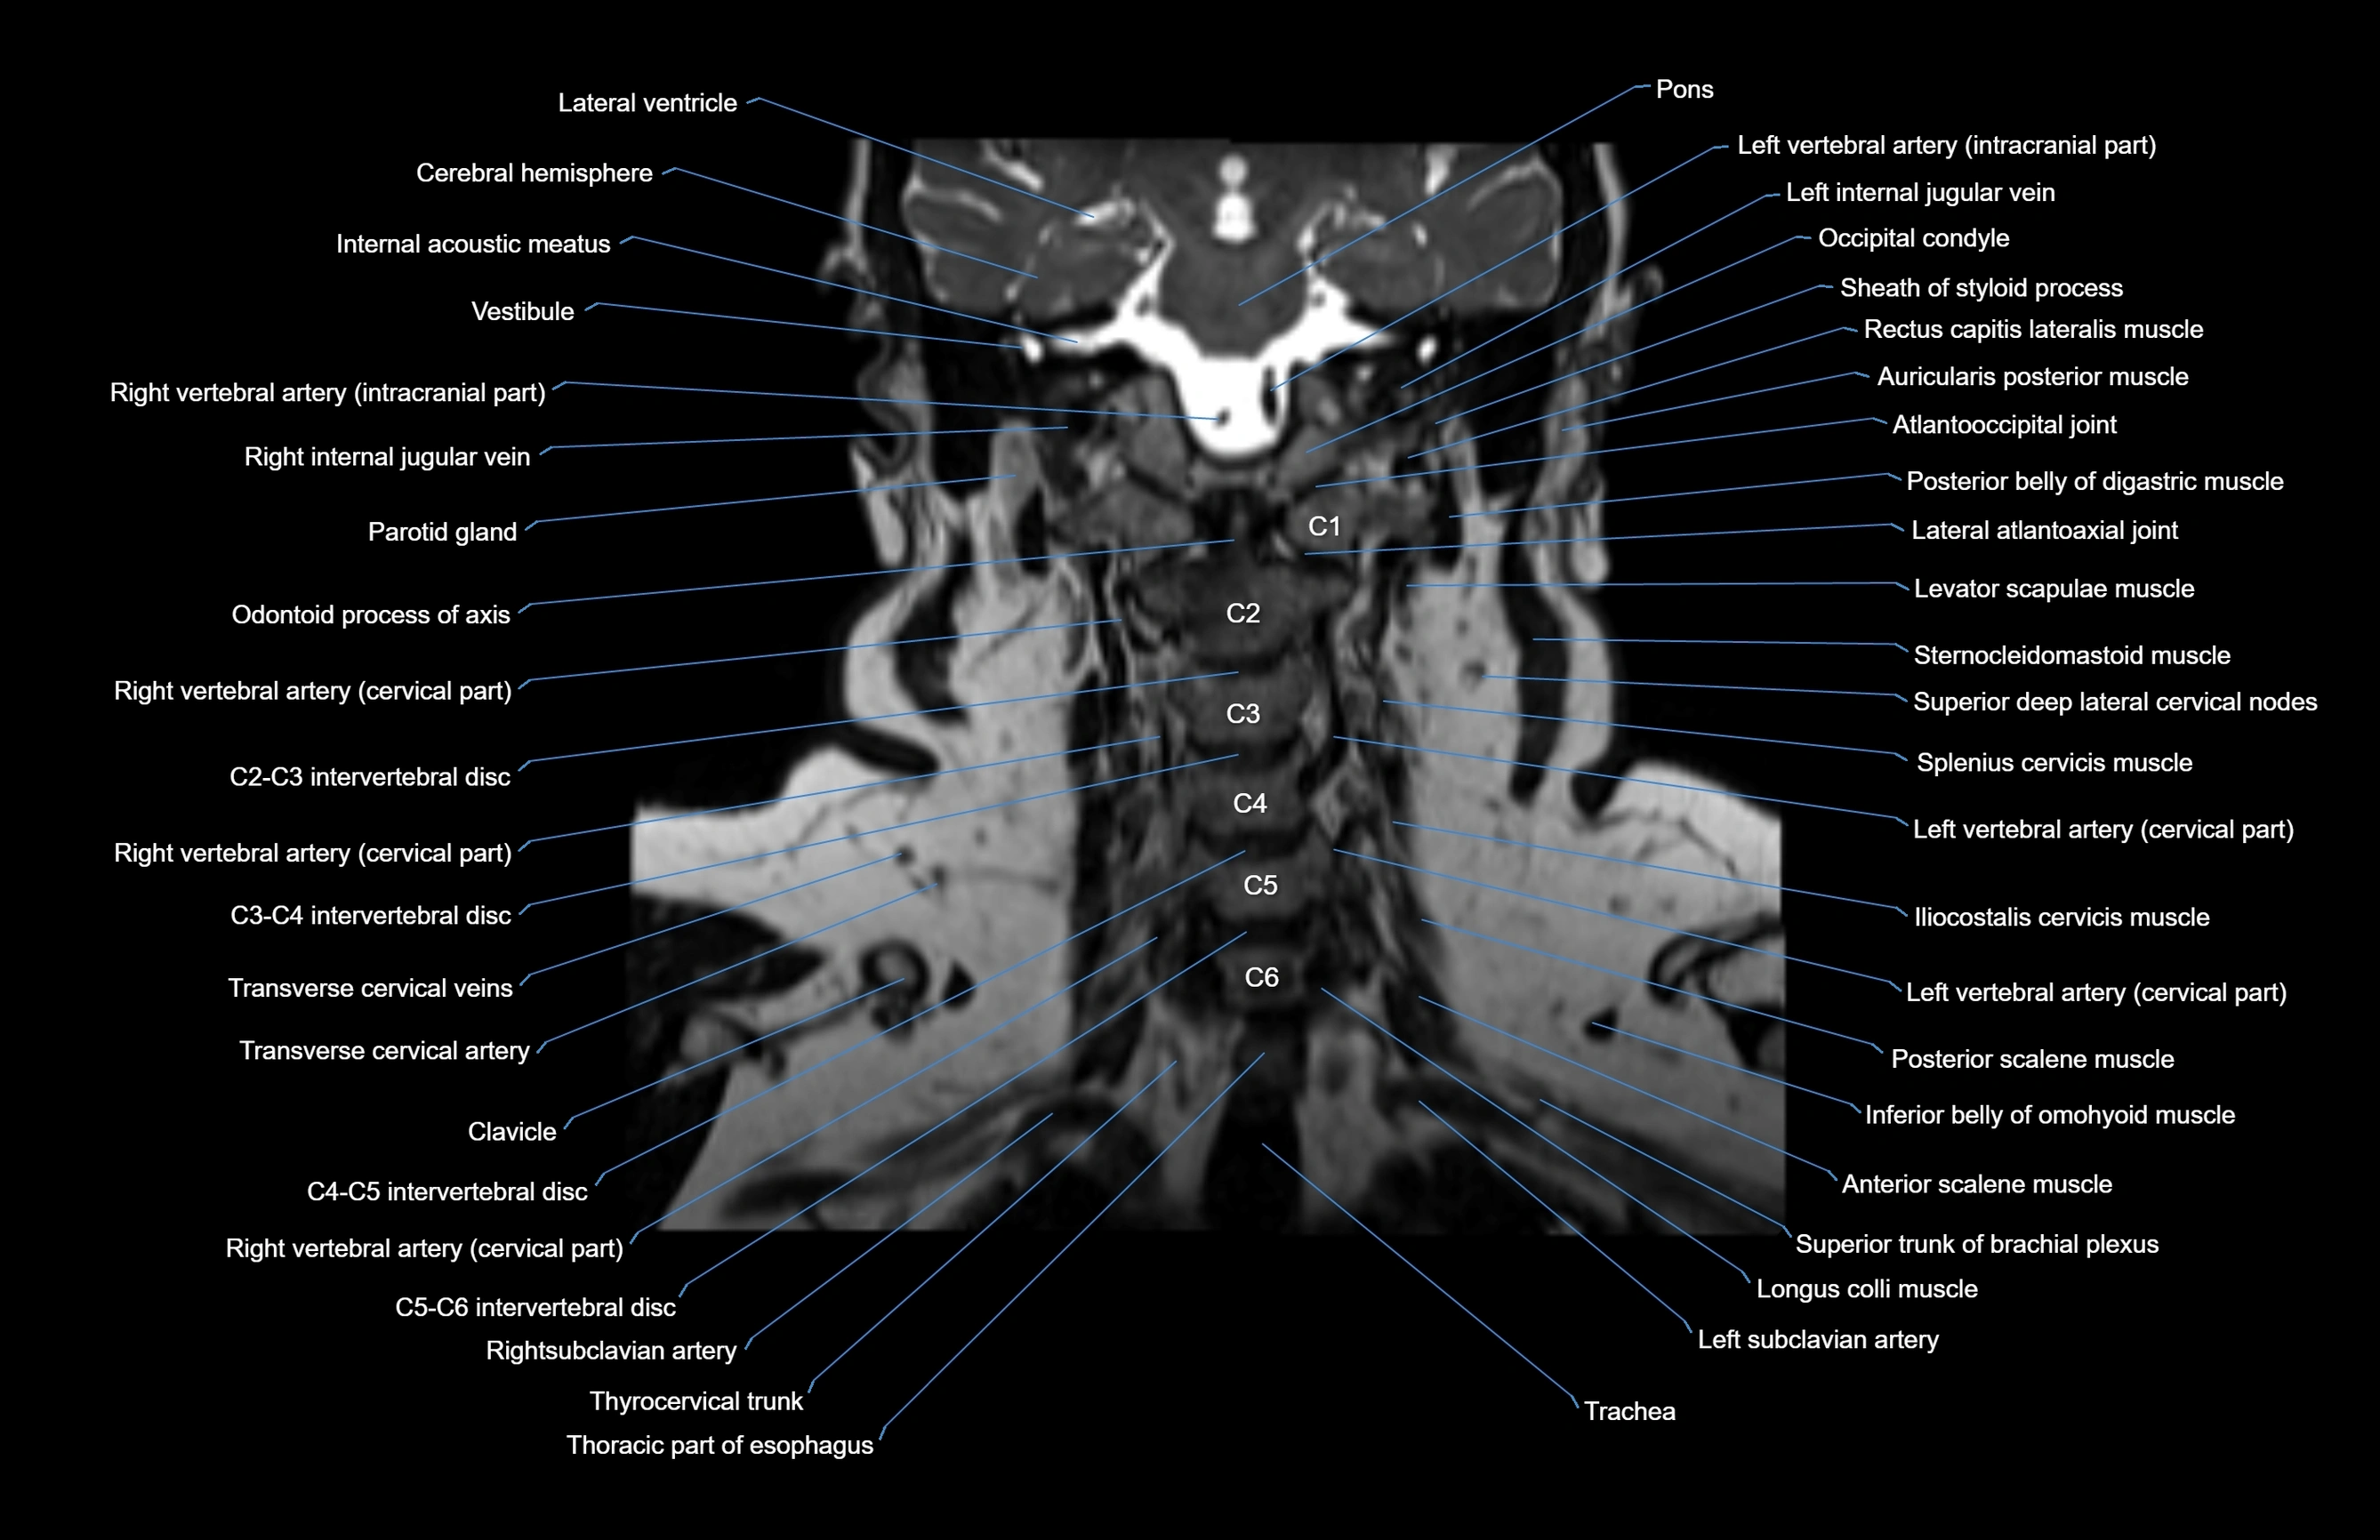

MRI images